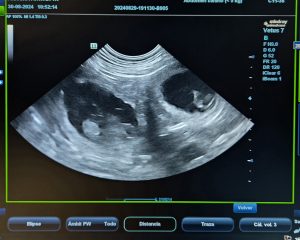

En este punto, ya se pueden distinguir los rasgos característicos de un cachorro, como la forma general del cuerpo, la cabeza, el tórax y el abdomen. Se inicia también la formación de los párpados, los dedos de las patas y los genitales, lo que permitirá, en pocos días, distinguir el sexo del feto mediante ecografía. El cordón umbilical ya está funcionando a pleno rendimiento, transportando oxígeno y nutrientes desde la madre.